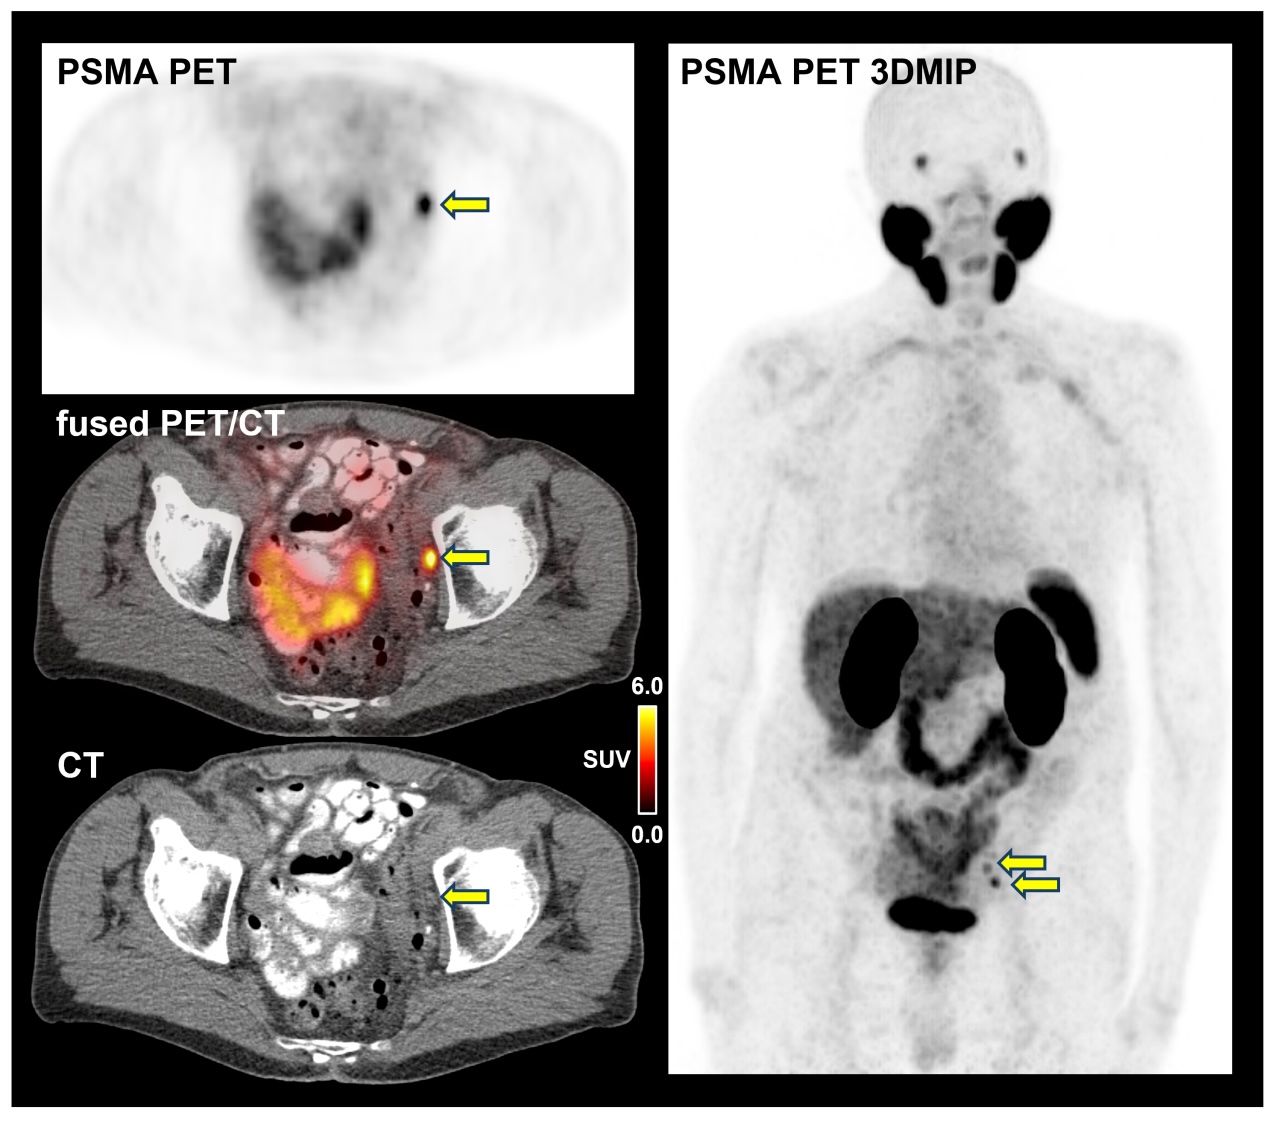

Пэт псма что это

Пэт псма что это 104 фотографий